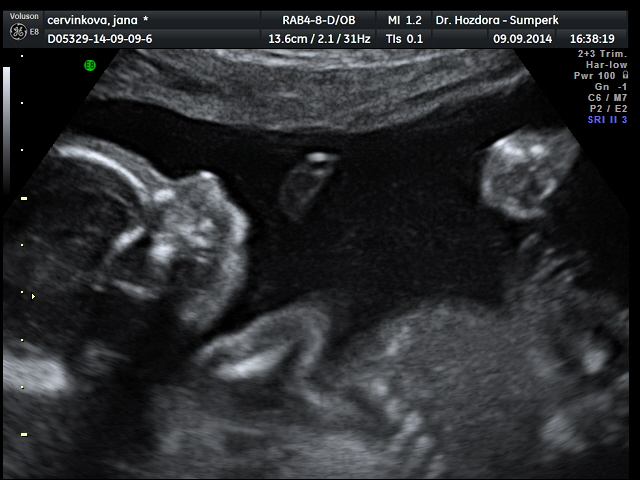

....po 25.tt koketuju s myšlenkou,že se objednám na 4D ultrazvukový záznam miminka. Jen se peru s financemi,stojí to 800kč,ale asi to dám,protože už rodit nebudu a když jsem čekala Fildu,tak takové vymoženosti nebyly.

Jani, úplně mě zalechtalo u srdíčka, ty fotky jsou nádherné. Já bych do 4D taky šla, je to sice dost peněz, ale je to na celý život